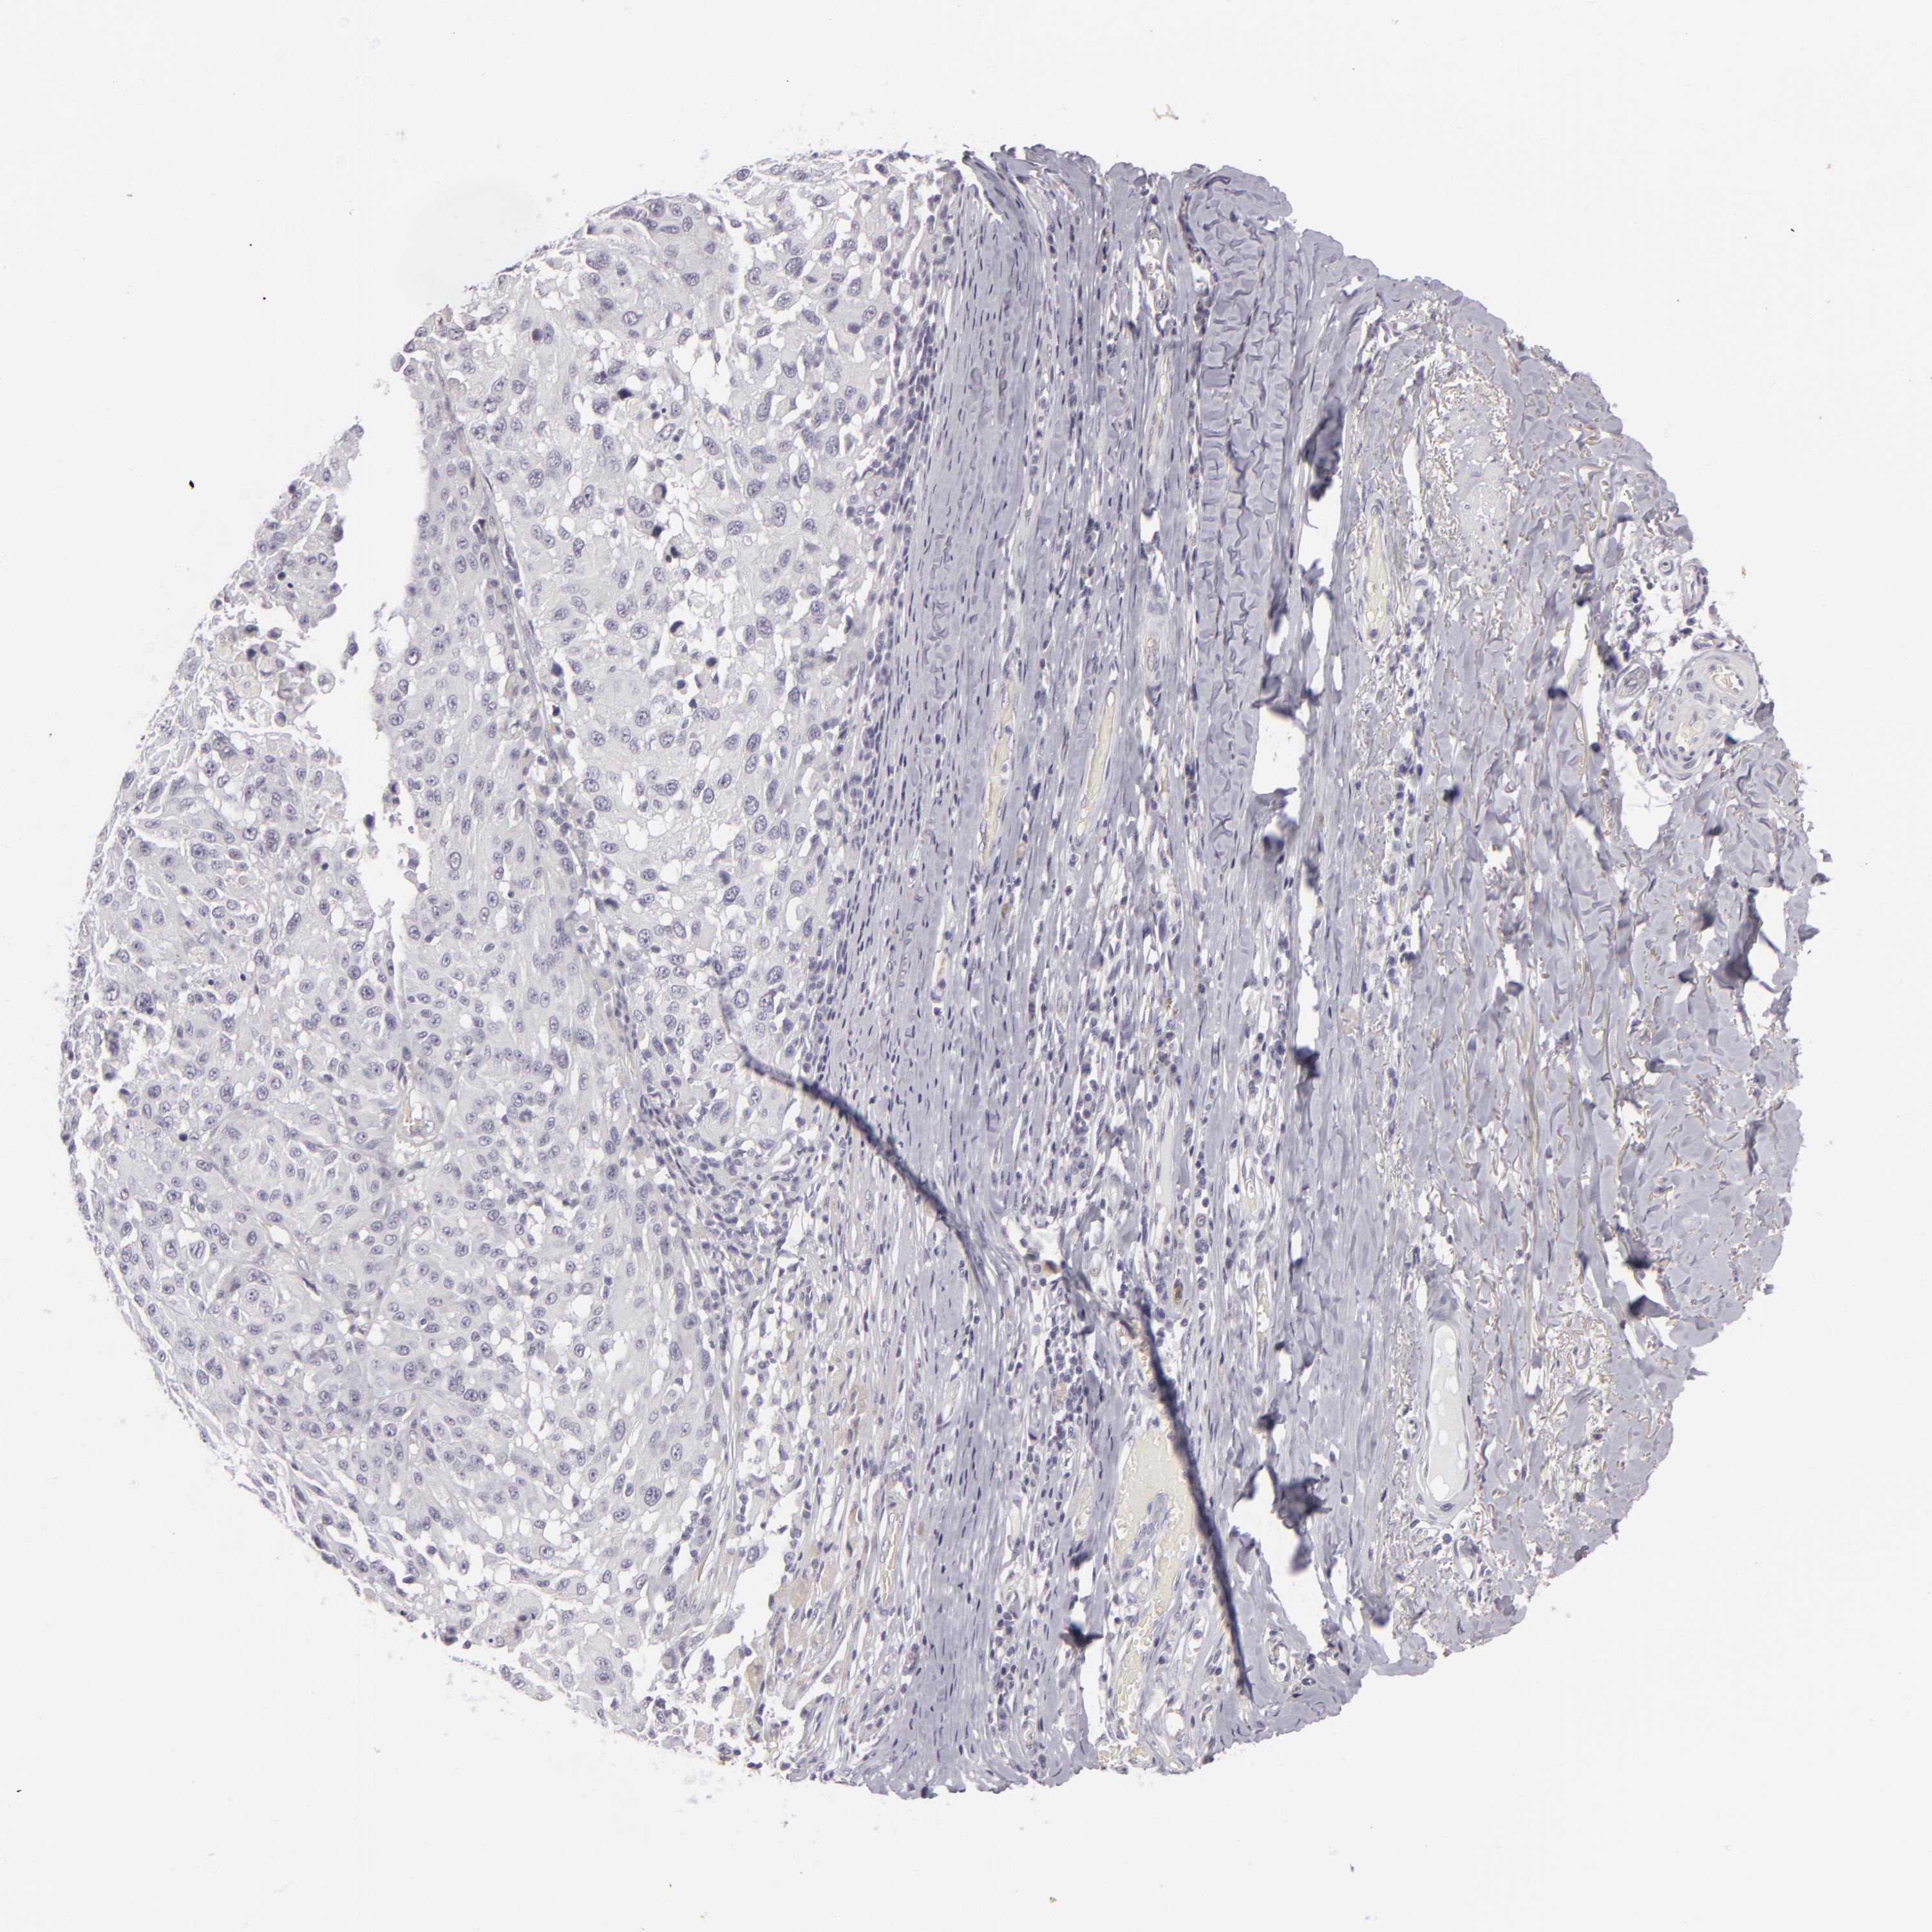

MELANOMA - Protein expressioni

A mouse-over function shows sample information and annotation data. Click on an image to view it in a full screen mode. Samples can be filtered based on level of antibody staining by selecting one or several of the following categories: high, medium, low and not detected. The assay and annotation is described here.

Note that samples used for immunohistochemistry by the Human Protein Atlas do not correspond to samples in the TCGA dataset.

Antibody stainingi

Antibody staining in the annotated cell types in the current human tissue is reported as not detected, low, medium, or high, based on conventional immunohistochemistry profiling in selected tissues. This score is based on the combination of the staining intensity and fraction of stained cells.

Each image is clickable and will lead to virtual microscopy that enables deeper exploration of all samples and also displays staining intensity scores, fraction scores and subcellular localization as well as patient and tissue information for each sample.

Antibody HPA032047

Antibody CAB002139

Malignant melanoma, NOS

Malignant melanoma, Metastatic site